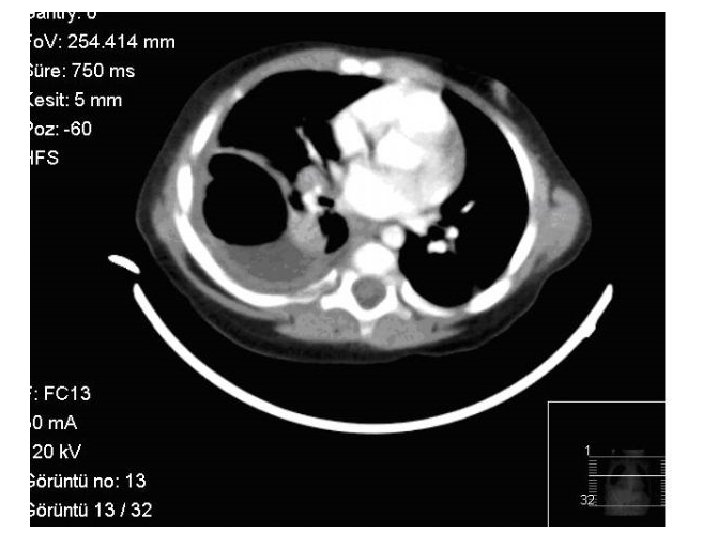

Toraks Tomografi(12/03/2013) • Sağ akciğer alt lobda içerisinde hava sıvı seviyesi izlenen kalın duvarlı ve duvar kontrastlanması gösteren abse ile uyumlu lezyon. • Sağ akciğer üst lob posterior ve alt lob superiorda pnömonik konsolidasyon. • Sağda plevral effüzyon.

• Akciğer grafisinde doku nekrozu gelişerek oluşan kaviteye pürülan materyalin boşalması ile hava-sıvı seviyesi şeklinde bir görünüm rastlanabilir. • Hava sıvı seviyesi akciğer apsesinde görülebildiği gibi ampiyemde de görülebilir bu nedenle daha ileri tetkiklere ihtiyaç vardır.

• Bilgisayarlı tomografi parankim lezyonlarını rahatlıkla ayırt edebilir. • Etken saptanmak istenirse nadir olarak transtrakeal aspirat veya transtorasik iğne aspirat tercih edilirken sık olarak plevral sıvı veya kan kültürü denenir. • Ancak kan kültürleri anaerob bakteriler açısından nadiren pozitiftir. • Balgam kültürü rahatlıkla yapılabilir fakat yanıltıcı olduğu unutulmamalıdır.